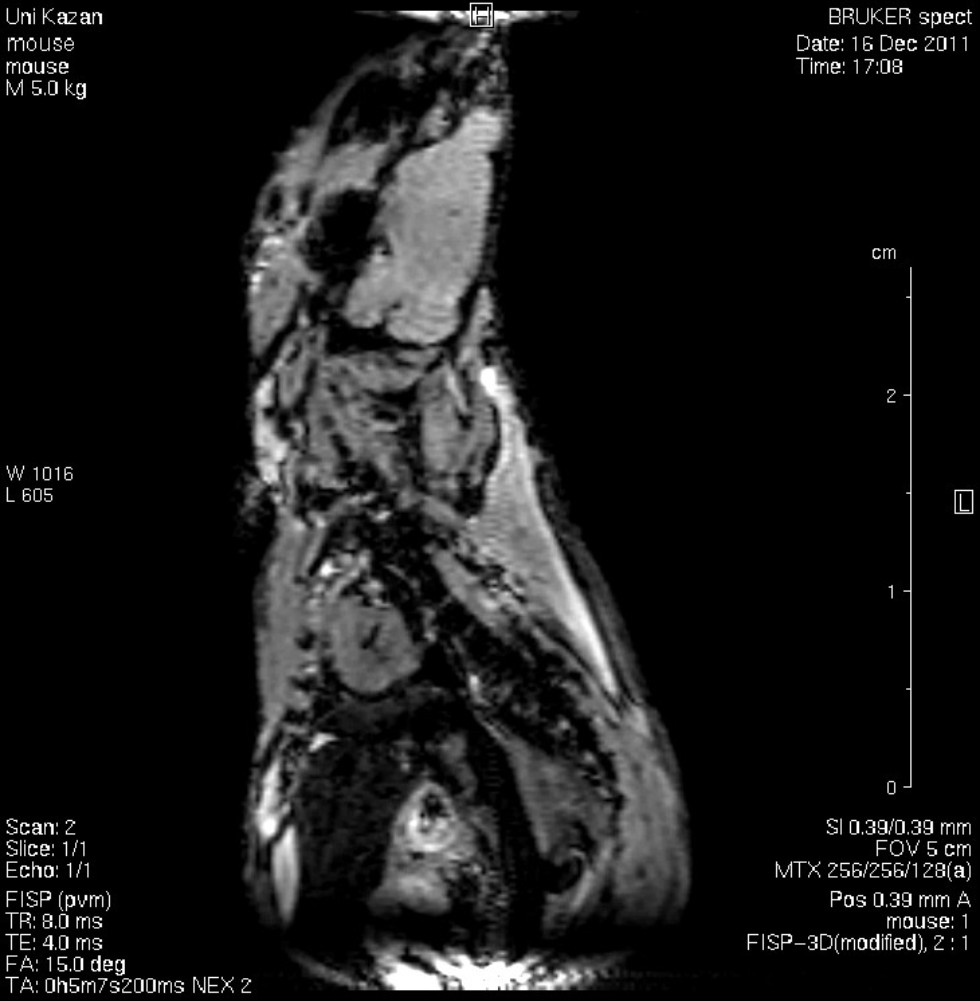

Ведущей кафедрой по специальности «Биотехнические системы и технологии» в Институте физики Казанского федерального университета является кафедра физики молекулярных систем, основанная в 1949 г. Институт физики славен своими традициями, уходящими в века. Деканом физико-математического факультета был великий математик Н.И. Лобачевский. Важнейшим открытием, сделанным в стенах физического факультета, является открытие Е.К. Завойским электронного парамагнитного резонанса в 1944 году. Это открытие определило развитие не только физического факультета, но и мировой науки на многие годы. Магнитно-резонансные методы исследования являются одним из основных научных направлений развития института.

Кафедра физики молекулярных систем ориентирована на развитие методов и разработку приборов магнитного резонанса для решения биологических, медицинских и прикладных задач. Значимость результатов применения методов магнитного резонанса в физике, химии и медицине подтверждается пятью Нобелевскими премиями (1944, 1952, 1991, 2002, 2003 гг). В учебной программе большое внимание уделяется изучению методов магнитно-резонанской томографии (МРТ), компьютерной томографии (КТ), позитронно-эмиссионной томографии (ПЭТ).

Обучение студентов основам физики происходит на современном лабораторном оборудовании. С первых лет обучения студенты привлекаются к научным исследованиям. Успешные защиты бакалаврских работ предполагают публикации результатов в научных журналах и участие в научных конференциях. Кафедра предоставляет студентам уникальную возможность выполнять учебную и научную работу на двух магнитно-резонансных томографах. В процессе обучения студенты получают также навыки практического проектирования и создания современной радиоэлектронной аппаратуры.